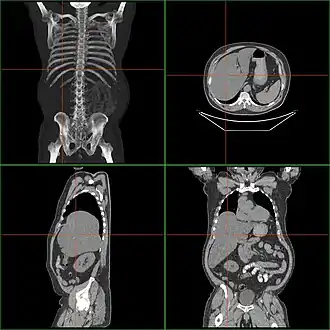

![]() Tomografía computerizada de afectado con hepatomegalia | ||

La inflamación hepática o hepatomegalia es la inflamación del hígado más allá de su tamaño normal.[1]